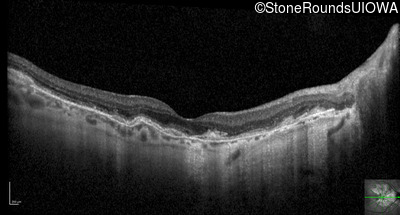

Optical Coherence Tomography - Left - 20/20 -1

Exemplar / OCT Stack